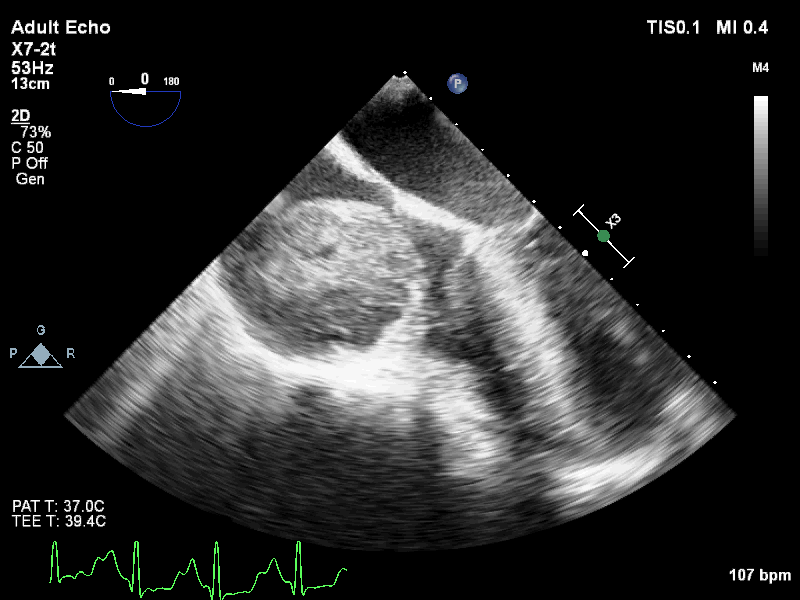

On further evaluation, the patient’s echocardiogram showed a 4.5 x 4.3 cm cystic tumor in the right atrium, hypertrophied obstructive cardiomyopathy with moderate left ventricular outflow tract obstruction, and good left ventricular function. She also underwent computed tomography (CT) and magnetic resonance imaging (MRI) of the chest, which revealed a neoplastic mass lesion, most likely right atrial myxoma.